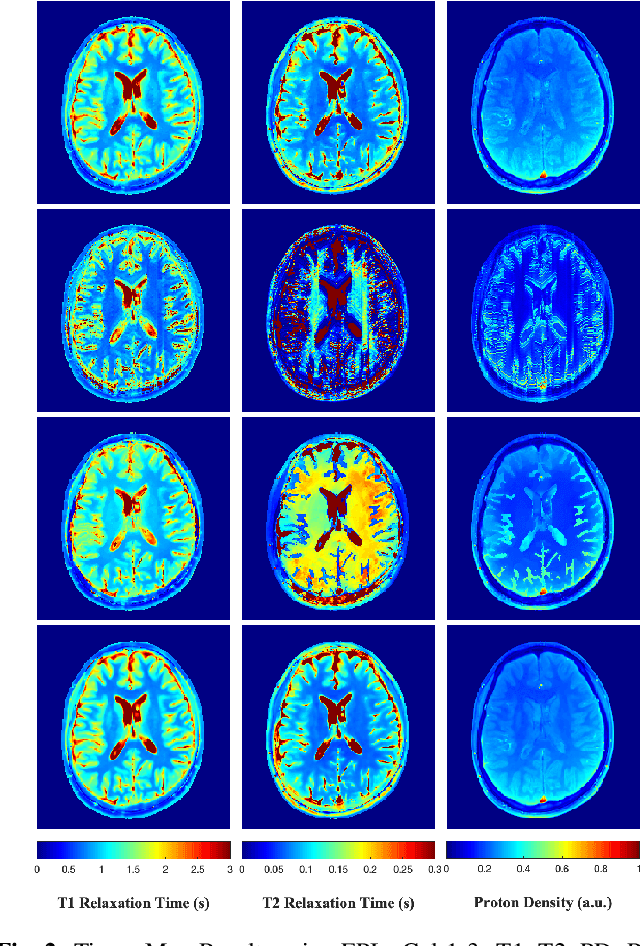

Abstract:Current spatiotemporal deep learning approaches to Magnetic Resonance Fingerprinting (MRF) build artefact-removal models customised to a particular k-space subsampling pattern which is used for fast (compressed) acquisition. This may not be useful when the acquisition process is unknown during training of the deep learning model and/or changes during testing time. This paper proposes an iterative deep learning plug-and-play reconstruction approach to MRF which is adaptive to the forward acquisition process. Spatiotemporal image priors are learned by an image denoiser i.e. a Convolutional Neural Network (CNN), trained to remove generic white gaussian noise (not a particular subsampling artefact) from data. This CNN denoiser is then used as a data-driven shrinkage operator within the iterative reconstruction algorithm. This algorithm with the same denoiser model is then tested on two simulated acquisition processes with distinct subsampling patterns. The results show consistent de-aliasing performance against both acquisition schemes and accurate mapping of tissues' quantitative bio-properties. Software available: https://github.com/ketanfatania/QMRI-PnP-Recon-POC